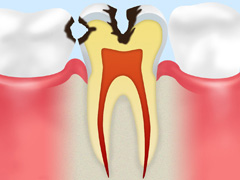

C1:エナメル質まで進行

歯の表面のエナメル質が溶かされた状態。黒い部分があらわれ始めますが、まだ痛みは感じません。

虫歯部分を削り、インレー(詰め物)でカバーします。ごく簡単な治療ですみます。